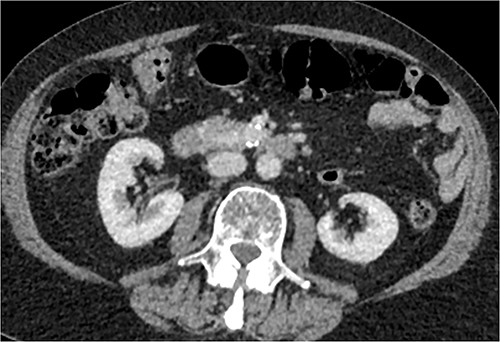

CT of abdomen and pelvis was performed, which revealed a 13 mm indeterminate lesion arising between the pancreatic uncinate process and the duodenum with coarse peripheral calcification, suspicious of primary pancreatic neoplasm or primary small bowel cancer (Figs 2–4).

Initial CT: sagittal view of the indeterminate pancreatic/duodenal lesion.